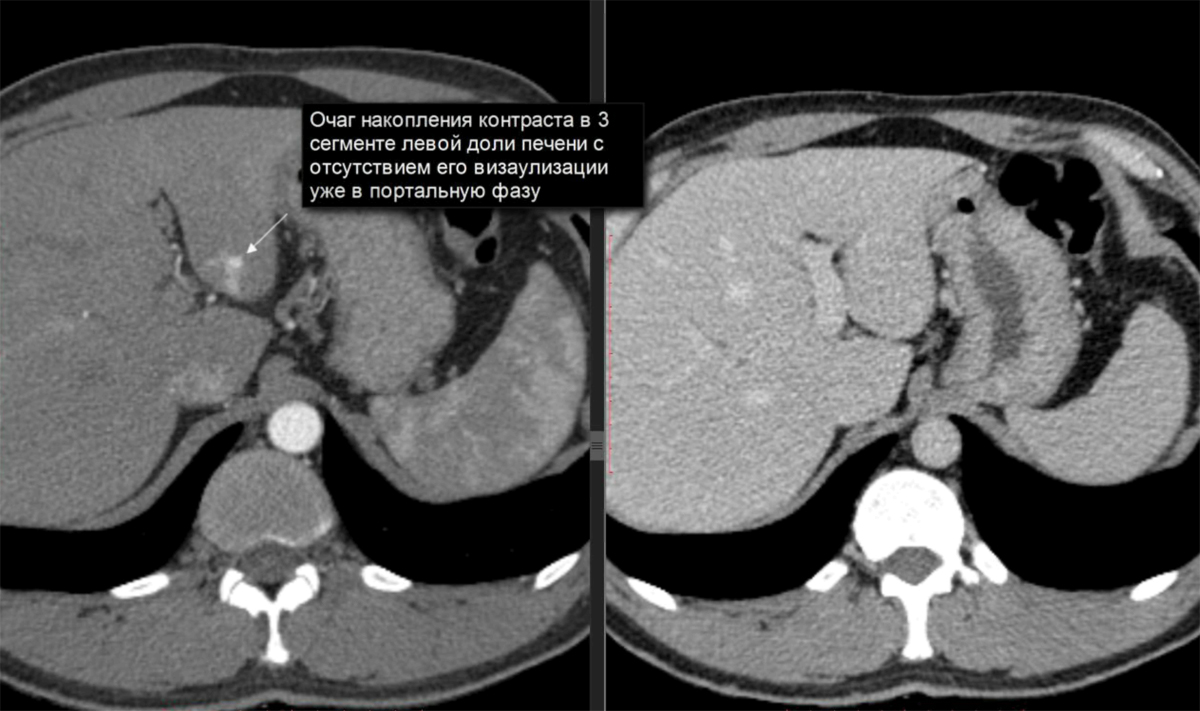

Как выглядит доля Риделя на УЗИ печени